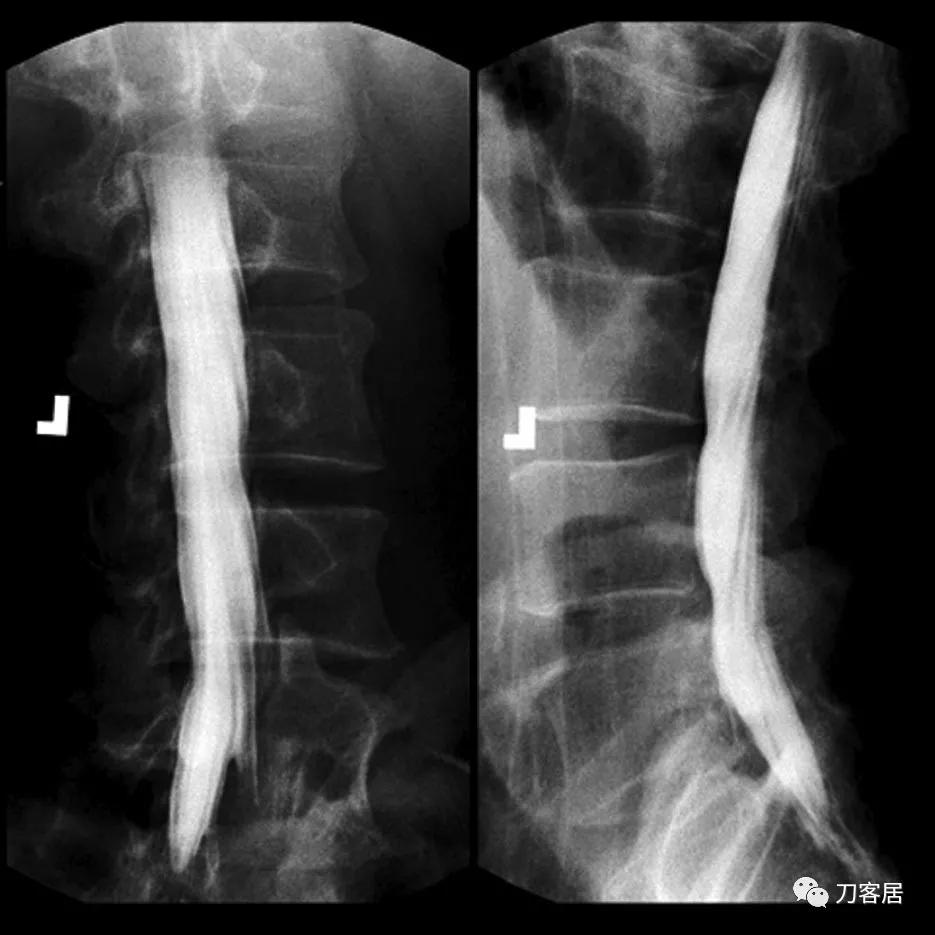

The patient reported back to the hospital within 24 h of release because of weakness in his lower limbs. His care was transferred to a medical specialist who treated him with a high dose of vitamin B-complex oral supplements. Although it was hoped that the supplements would revitalize damaged neurons, no such treatment proved fruitful. Three days after the incident, a lumbar puncture was done to obtain cerebrospinal fluid specimen and to perform a myelogram. Results of cerebrospinal fluid analysis were considered normal, with elevated protein concentrations (54 mg/dl [normal=15–45 mg/dl]). Lateral and oblique views of the lumbar myelogram showed mild external compression on the thecal sac at L3–L5, most likely the result of disc bulging at those levels. However, this type of radiographic finding is common in significant proportion within a healthy, asymptomatic population. Vertebral heights and disc spaces were likewise normal (fig. 2).

因为下肢无力,患者出院后24小时内又返回医院。请另一医学专家会诊,给予大剂量复合维生素B口服治疗,希望能有效治疗受损神经元,结果无效。三天后,行腰椎穿刺以获取脑脊液并进行脊髓造影。脑脊液分析结果正常,但蛋白质浓度升高(54毫克/分升[正常=15–45毫克/分升])。腰椎侧位和斜位脊髓造影显示L3–L5处硬膜囊轻微受压,很可能系由该部位椎间盘膨出所致。然而,在大部分健康、无症状的人群中,这种轻微受压很常见。椎体和椎间隙高度均正常(图2)。

Fig. 2. Lumbar myelogram taken on third day after medication error. In preparation for transurethral prostate resection for benign hyperplasia, an intrathecal injection of 3 ml aminophylline was administered instead of bupivacaine (bupicain), 0.5%.

图2。用药错误后第三天进行腰椎脊髓造影。在准备经尿道前列腺电切术治疗前列腺增生时,误将3毫升氨茶碱当作0.5%布比卡因进行鞘内注射。